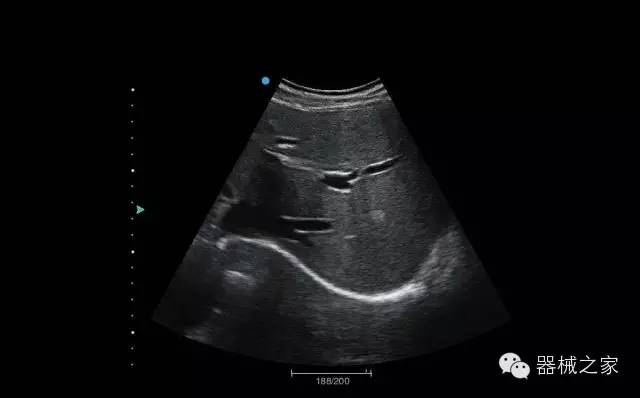

經(jīng)典產(chǎn)品:Apogee 1000

臨床圖片賞析

結(jié)甲

腎臟血流

肝血管瘤